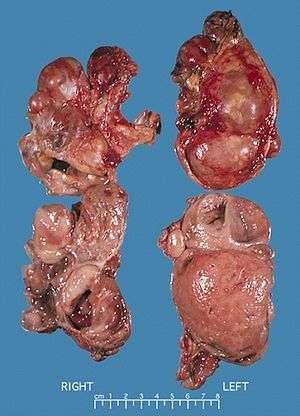

| Bilateral pheochromocytomas associated with Multiple endocrine neoplasia type 2 | |

Pheochromocytoma occurs in 33-50% of MEN2 cases.[3]

In a review of 85 patients 70 had Men2A and 15 had Men2B.[3] The initial manifestation of MEN2 was medullary thyroid carcinoma in 60% of patients, medullary thyroid carcinoma synchronous with pheochromocytoma in 34% and pheochromocytoma alone in 6%. 72% had bilateral pheochromocytomas.